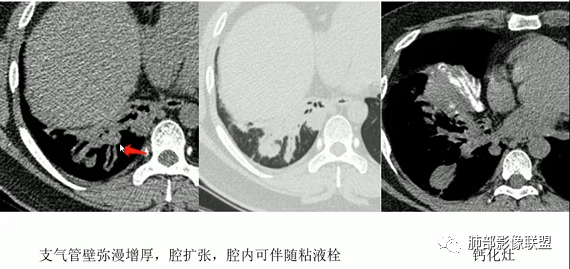

指套征影像特点:

1、支气管粘液栓的表现∶多位于肺门的外侧,紧邻肺门,少数位于肺野外周,走行与正常支气管走行类似,而原来相对应区域的支气管缺失或阻塞。呈分支状或指套状结构,近端闭锁,不与支气管相通,与CT扫描层面平行时为"V"形、"Y"形或多个分支条状,与CT层面垂直时为类圆形结节状,MSCT应用MPR可行任意角度重组观察黏液栓的形态及其与近端支气管、血管的关系。黏液栓多为水样密度或软组织密度(较粘稠的黏液).但增强扫描无强化;内可有气体影,形成液气平面。伴随肺动脉细小。

2、间接征象∶周围肺气肿或阻塞性炎性改变。绝大部分都伴随不同程度的肺气肿,常见的是较大面积的肺气肿,其内血管比较纤细,也有报道可以不伴随肺气肿,但是罕见。

ABPA影像:1、中心型支气管扩张,常常双侧较对称,一般以段、亚段为主,支气管壁增厚,腔内有粘液栓,呈指套状或牙膏状影,粘液栓高密度(约30%),无强化。2、小气道异常∶小叶中心细支气管扩张并充有粘液——树芽征。3、伴随征象∶肺内斑片状、结节状高密度影,呈游走性;扩张支气管远端可伴有阻塞性肺气肿、肺不张,肺纤维化、局部胸膜增厚或积液。4、治疗好转粘液栓消失,扩张支气管的转归∶ 部分不变化,部分较前稍缩小,很少一部分可以恢复正常,一般壁稍增厚。

上图,ABPA,支气管扩张、腔内指套样粘液栓,部分粘液栓呈高密度,较具特征性。

上图,支气管结核。病灶多灶性、多态性。支气管中近端受累,支气管壁增厚不均匀,狭窄后扩张,伴随树芽征、钙化。